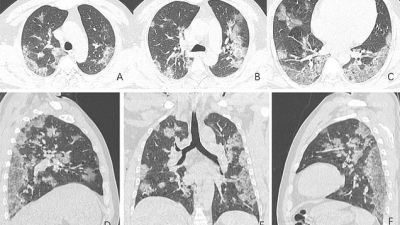

The scans show white patches in the lower corners of the lungs which indicates what radiologists call ground glass opacity - the partial filling of air spaces.

Such abnormalities identified by doctors in the scans of coronavirus patients are similar to those found in patients suffering from SARS and MERS.

The scan of a 45-year-old woman from Sichuan Province in China who tested positive for COVID-19 after returning from Japan shows white patches and a 'reversed halo sign' in the left upper lobe of her lung.

The extended white patches seen in the scans were also identified with severe acute respiratory syndrome (SARS) and Middle East respiratory syndrome (MERS).

Both are also classified as coronaviruses and SARS resulted in 8,000 cases and 774 deaths in China from November 2002 to July 2003.